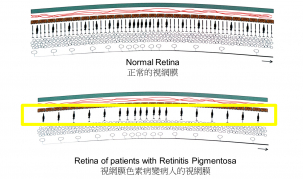

The Eye Institute of The University of Hong Kong (HKU) Li Ka Shing Faulty of Medicine performed the first implantation of subretinal microchip in Asia to a Chinese patient who was visually impaired due to degenerative condition retinitis pigmentosa (RP). The early result of the surgery is highly satisfactory and the patient has gained sight, including seeing light and dark and being able to read letters projected on a screen. The microchip was developed by Retina Implant AG ("Retina Implant"), a leading developer of subretinal implants for the visually impaired. Subsequent to the first and second phases of clinical trials conducted in Germany, the operation performed by HKU team is the first successful case outside Germany to apply the new technology on a patient, kicking off the phase 3 international trial of this subretinal implants.

The subretinal microchip implantation involves placing a 1500-electrode microchip just below the retina, specifically in the macular region. Results of Retina Implant's first human clinical trial were published in the prestigious peer-reviewed journal Proceedings of the Royal Society B and showed placement of the implant below the retina, in the macular region, provided optimum visual results allowing patients to recognize foreign objects and to read letters to form words.

Learning from the experience of the first implantation, Professor David WONG and his team find there are many research questions waiting to be answered. Professor David WONG says, "So far, we know that the retinal chip can be safely put inside an eye. The surgery is challenging and can take many hours to perform. We already know that for the chip to work best, it has to be precisely placed underneath the macula. What we do not know is which type of patients would benefit the most from the surgery. There are many forms of RP. Many are familial. We do not know whether the duration of blindness makes any difference to the prognosis. To be totally convinced of the effectiveness of the surgery, we are selecting patients who are totally blind. We prefer to operate on patients who have no light perception or those patients who cannot utilize what light they see for navigational purposes."

Dr Ian WONG Yat-hin, Clinical Assistant Professor, Eye Institute, The University of Hong Kong Li Ka Shing Faculty of Medicine, said that retinitis pigmentosa is untreatable and patients will gradually go blind.